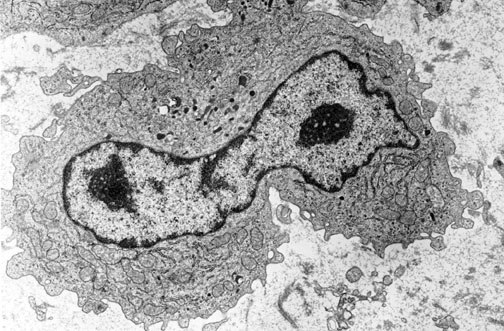

| A macrophage has abundant cytoplasm and an oblong nucleus. The macrophage is involved with phagocytosis. Macrophages function as the "clean-up crew" in inflammatory reactions to remove devitalized and unwanted cells, tissues, infectious agents, and foreign material. |